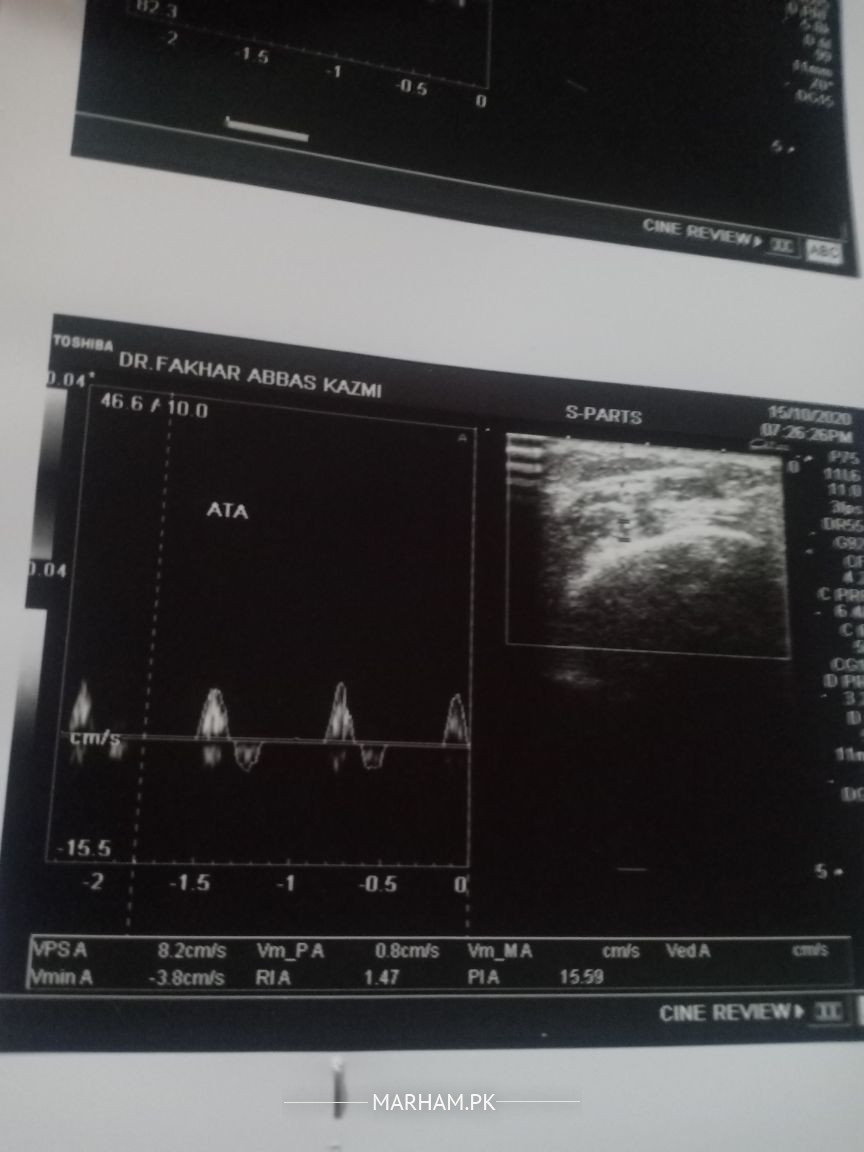

mohtaram Docter sahiban AoA. Moderately sever peripheral vascular diease in bilateral lower limbs with changes more marked on right side. ye ultrasound ka result hy .legs mn shadeed pain hota hy .shugar b hy .reports attach hn .plz rahnumai farmaen k kis dr sy treatmint kerwana chahye . mn ap ko reports or jo hn medecien ly rahy hn wo b send kr raha hn ye meri wife ko problem hy .Thanx

dear patient, you have deceased vessels due to your diabetes.

pl book appointment for consultation.

you may need further tests to guide u to proper treatment.